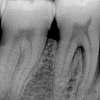

Luukadu agressiivse parodontiidiga patsiendil

Agressiivset parodontiiti iseloomustab puberteedieas või 20-ndates algav igemete kinnitus kudede ja alveolaarluu hävimine. Lokaliseerunud vormi puhul on esmased kolded esimeste jäävmolaaride, esimeste premolaaride ja lateraalsete intsisiivide piirkonnas.

Iseloomulik on progresseeruv hamba kinnituskudede kadu koos sügavate taskute moodustumisega ning väljendunud hammaste liikuvus ning reast nihkumine.

Igemed võivad olla suhteliselt väheste põletiku nähtudega, mis seletab ka hilist diagnoosimist, kui haigus on juba kaugele arenenud. Katu kogunemine on vähene. Iseloomulik on vähe või üldse mitte hambakivi.